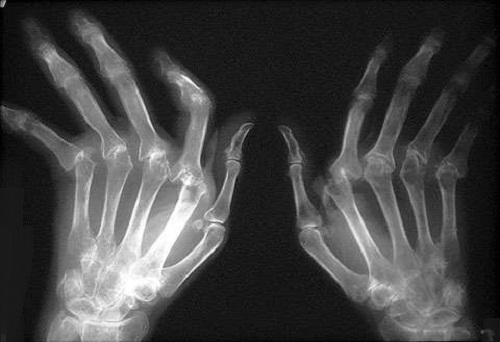

Artrite

Como já sabemos, a artrite é causada pela alteração ou desgaste da cartilagem. Essa nada mais é do que o tecido que reveste as articulações. Também é responsável por fazer com que os movimentos sejam muito mais suaves e não causem atrito entre os ossos.

Até o momento se desconhece a causa da artrite. Além disso, não existe nenhum medicamento que a cure, já que são usados somente anti-inflamatórios e comprimidos para a dor.

Porém, é importante que, principalmente as pessoas que sofrem com esta doença em maior ou menor grau de agressividade, saibam que a causa de sua dor ser em grande parte pela falta de hidratação.

Isso porque as cartilagens contêm uma grande quantidade de água para poder manter as articulações bem lubrificadas e isto permite que os ossos não rocem entre si. Assim os movimentos são muito mais suaves, sem causar os danos típicos da artrite.